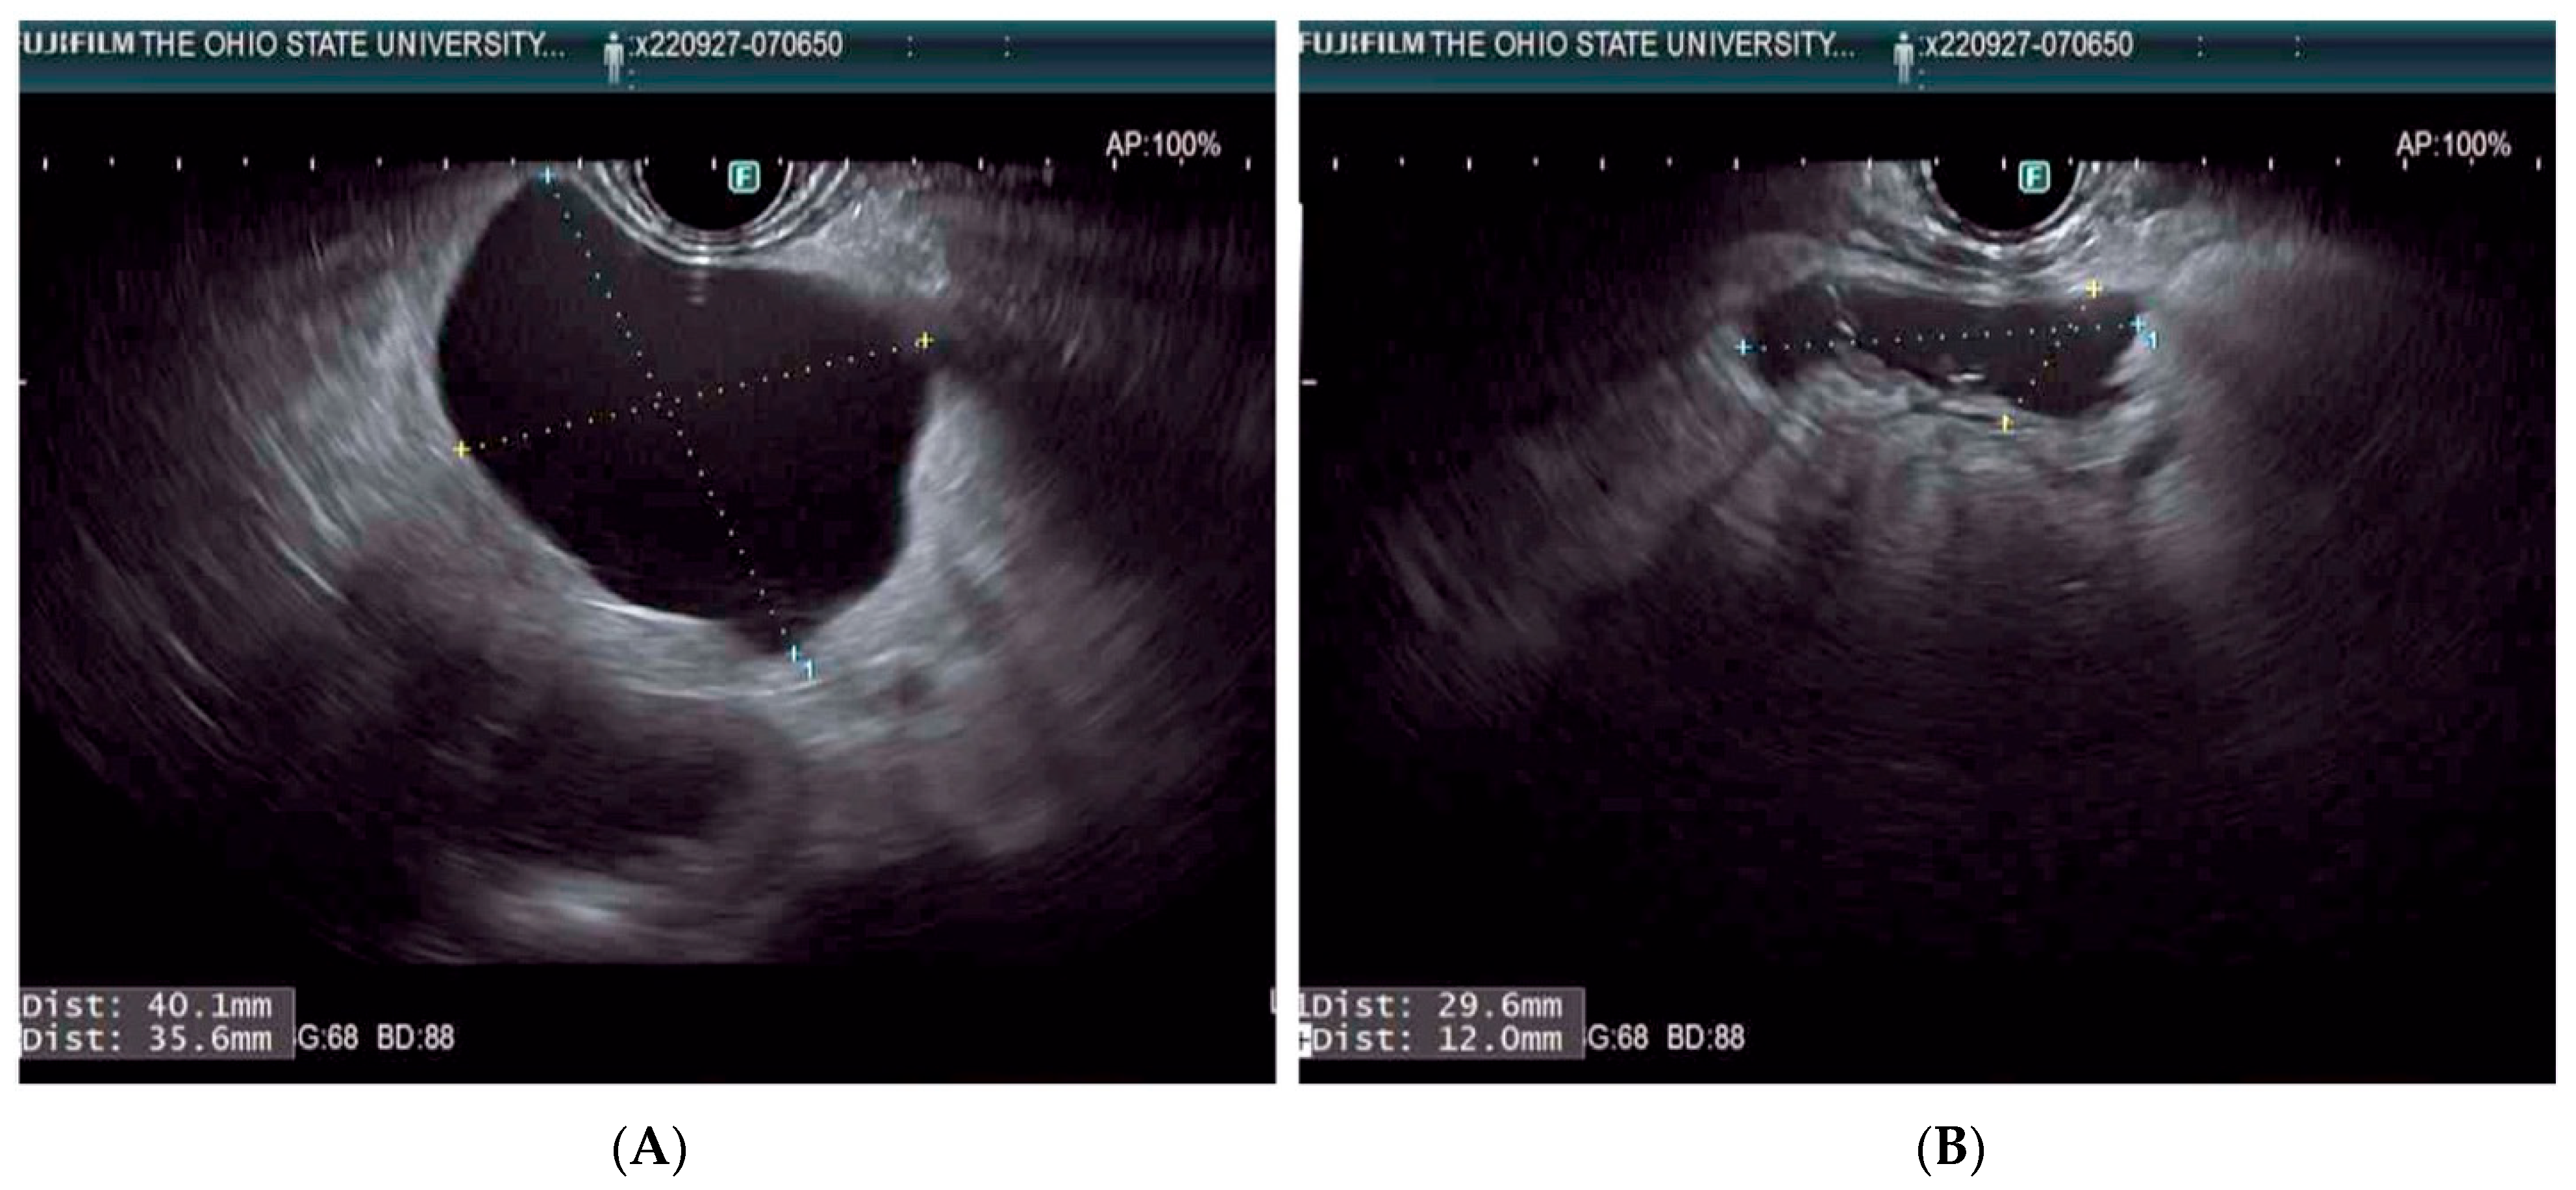

- Krishna, S.; Ardeshna, D.; Woods, E.; Tsung, A. An update on EUS-guided ablative techniques for pancreatic cystic lesions. Endosc. Ultrasound 2022, 11, 432. [Google Scholar] [CrossRef] [PubMed]